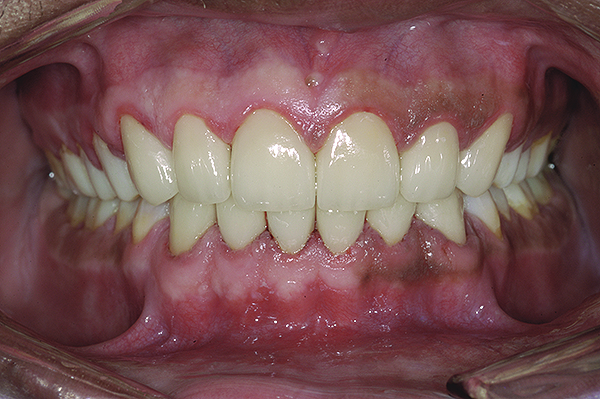

Figure 5. Preoperative 1:1 retracted frontal view.

Figure 5